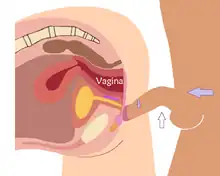

Penile fracture is a relatively uncommon clinical condition.[7] Vaginal intercourse and aggressive masturbation are the most common causes.[4] A 2014 study of accident and emergency records at three hospitals in Campinas, Brazil, showed that woman on top positions caused the greatest risk with the missionary position being the safest. The research conjectured that when the receptive partner is on top, they usually control the movement and are not able to interrupt movement when the penis suffers a misaligned penetration. Conversely, when the penetrative partner is controlling the movement, they have better chances of stopping in response to pain from misalignment, minimizing harm.[7]